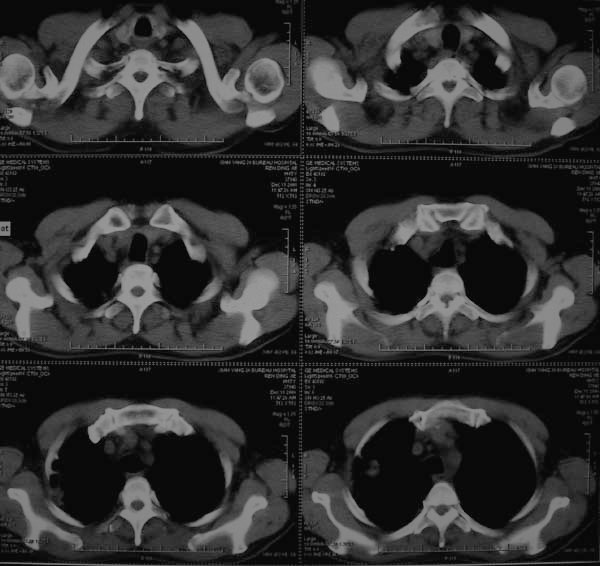

标题: CT17173:M65Y,咳嗽一月。请会诊 [打印本页]

标题: CT17173:M65Y,咳嗽一月。请会诊